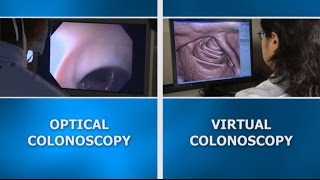

difference entre un coloscanner et un scanner abdominale standard Colonoscopy screening: Virtual vs. optical colonoscopy

Colonoscopy screening: Virtual vs. optical colonoscopy Should you have a virtual colonoscopy?

Should you have a virtual colonoscopy? Virtual Colonoscopy Screening for Colorectal Cancer

Virtual Colonoscopy Screening for Colorectal Cancer Is there an X-ray test to screen for colon cancer? - Dr. Lisa Boardman

Is there an X-ray test to screen for colon cancer? - Dr. Lisa Boardman

difference entre un coloscanner et un scanner abdominale standard Colonoscopy screening: Virtual vs. optical colonoscopy

Colonoscopy screening: Virtual vs. optical colonoscopy Should you have a virtual colonoscopy?

Should you have a virtual colonoscopy? Virtual Colonoscopy Screening for Colorectal Cancer

Virtual Colonoscopy Screening for Colorectal Cancer Is there an X-ray test to screen for colon cancer? - Dr. Lisa Boardman

Is there an X-ray test to screen for colon cancer? - Dr. Lisa Boardman